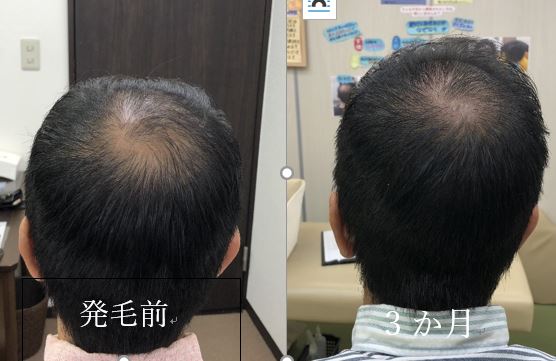

★発毛・薄毛部門からのお知らせ★

⚡薄毛・育毛にお困りの方に朗報です⚡

確実に満足のいく結果を出します!

あなたにとって「人生最後の発毛治療」にしましょう。

本気で私もあなたと向き合います!

※「臍帯幹細胞の薄毛治療カウンセリングを受けたい」

とご連絡ください!

当院の発毛治療はオンラインでも対応しております。